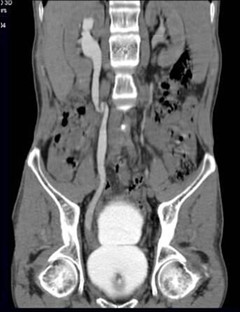

3.CT泌尿系成像技术(CTU) CTU一种无创伤性检查,操作简便,扫描时间短,图像分辨率高、具有多种成像方式、多方位观察病变、无需腹部加压;CT强大的后处理技术使得可根据临床需要,通过CPR、MPR、MIP和VR等重组图像来显示泌尿系统全程,在一定程度上尚可反映肾脏的分泌,排泄功能,对病变的显示更清晰直观,集合了传统CT和IVP及B超的优点,较其他泌尿系检查方法更容易做出定性诊断。在泌尿外科疾病的诊断,鉴别诊断上有重要的应用价值。